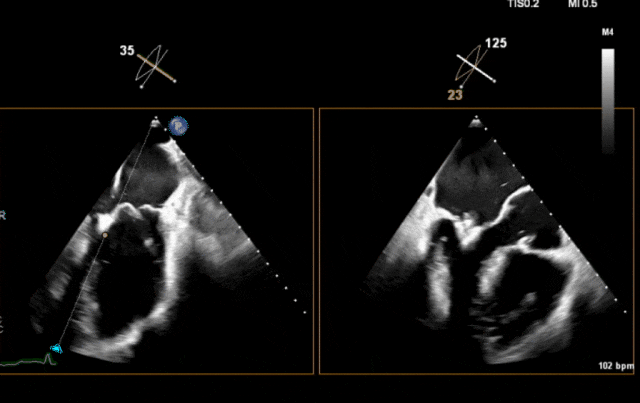

第二枚夹合器夹闭后超声

紧接着,术者将第三NeoNova® C6送至稍外侧位置并操作瓣叶夹合,超声示外侧残余反流、脱垂,推测瓣叶夹持量欠佳;重新捕获瓣叶后,超声示残余反流明显减少,组织桥稳定,最终成功紧贴前两枚夹合器于2偏1区位置解离第三枚C6。心脏彩超示二尖瓣轻度反流,反流程度由5+降至1+,术后即刻跨瓣压差5mmHg。

依据术前策略,将第二枚NeoNova® C6夹合器送至第一枚C6外侧,使两枚夹合器临近,夹闭第二枚C6后超声示两枚夹合器紧邻,组织桥稳定,跨瓣压差2mmHg;但外侧仍残余反流、脱垂,因此决定植入第三枚夹合器。